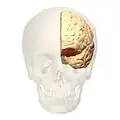

front view.

front view. -